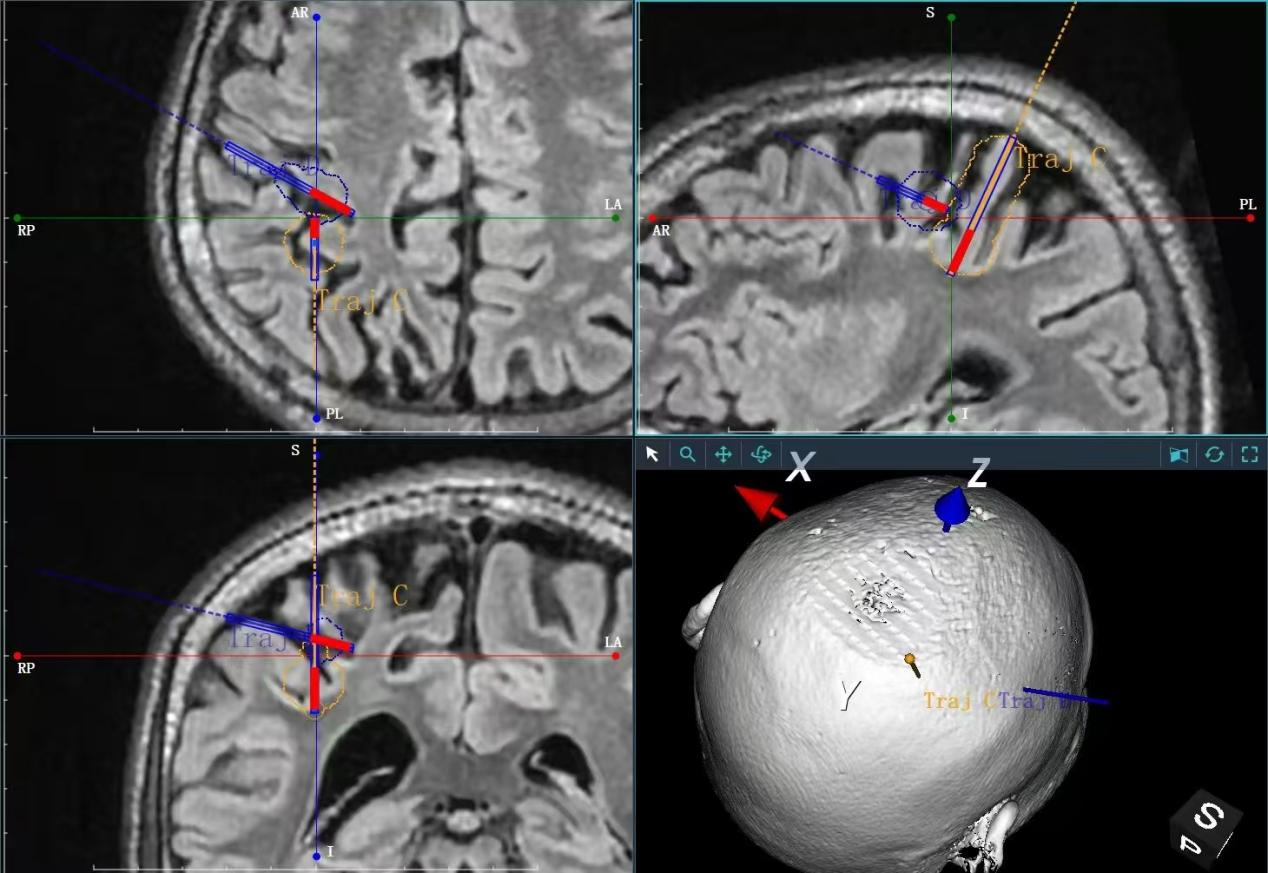

手术中,医生仅在患儿颅骨上钻开一个约3毫米的微孔,随后将直径不足2毫米的柔性激光光纤植入颅内。在磁共振全程实时引导下,光纤被精准送达病灶核心。

激光治疗过程图示

在消融阶段,系统以41℃~45℃的温度对病灶进行可控加热。术中磁共振连续扫描,实时生成三维温度分布图并投射于手术屏幕,使医生能够同步观察消融范围,确保其严格限定在病灶边界内,不损伤周边正常神经纤维。